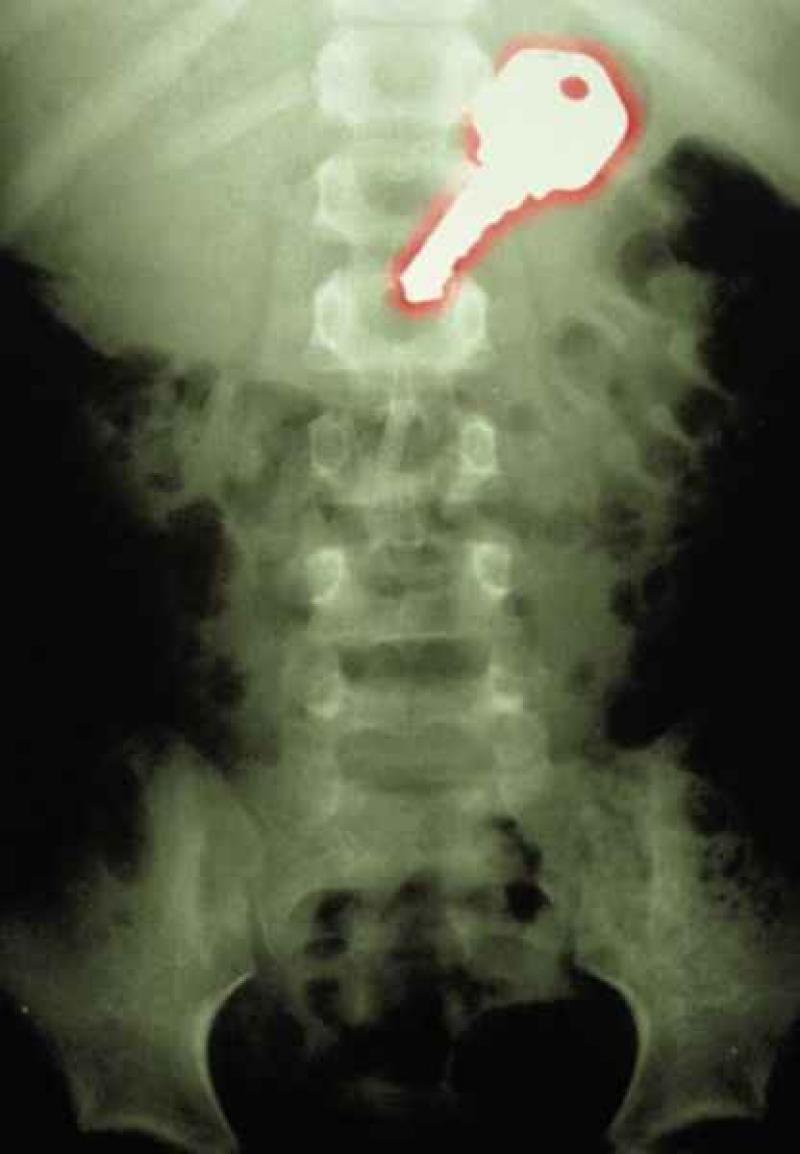

Röntgenfoto's zijn een medische uitvinding die ons al decennia lang helpt. Ze geven een nieuw gezichtspunt als het gaat om het vinden en behandelen van inwendige verwondingen. De machines kunnen opmerkelijke beelden vastleggen van het menselijk lichaam en ze documenteren vaak gruwelijke verwondingen. Een wonde van iemand zien, is al erg, maar als je ook kan zien wat de schade in het lichaam is, dat is nog veel erger. We hebben 12 tegelijk fascinerende, gruwelijke en hilarische röntgenfoto's op een rijtje gezet. Stel jezelf maar eens de vraag hoe iemand ooit aan die verwondingen is gekomen. We beginnen nog rustig.